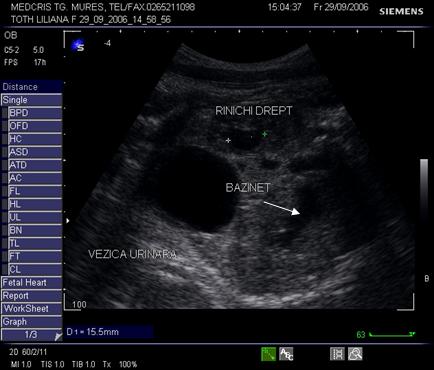

Fig. nr. 273. Dilatatie pielocaliceala renala fetala, unilaterala, la 16 sapt.( sageata)

Fig. nr. 274. Sectiune transversala fetala la nivel lombar, 23 sapt., linia verde indica rinichiul fara dilatatie, cu sageata se remarca dilatatia pielocaliceala evidenta controlaterala

Fig. nr. 275. Dilatatia pielocaliceala din figura precedenta , intr-o sectiune parasagitala fetala, cu axul lung renal.

Fig. nr. 276. Megaureter, la 23 sapt la acelasi fat din figurile precedente.

Fig. nr.277. Dilatatie bilaterala bazinetala renala la 28 sapt, sectiune transversala lombara, fat cu sindrom de valva uretrala posterioara

Fig. nr.278. Sindrom de valva uretrala posterioara, la fatul de 28 sapt. sex masculin, se remarca dilatatia bilaterala bazinetala moderata, vezica urinara destinsa,

Fig. nr .279. Sarcina de 32 sapt., cu bazinet renal minim dilatat. ( cu linia rinichiul pol inferior,cu sageata pielonul )